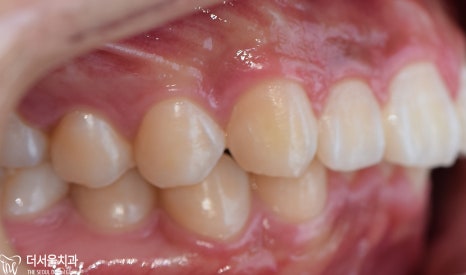

구강 사진을 보면

윗니가 뻐드러져 있는 걸 볼 수 있으며

아랫니는 치열이 고르지 못한 것을 알 수 있었습니다.

정면과 측면에서 봤을 때

하악 전치부가 거의 보이지 않을 정도로

심한 과개 교합을 양상을 나타내고 있었습니다.

전체적으로

문제점을 종합해 보면

2급 부정교합과 과개 교합을 나타내고 있었습니다.